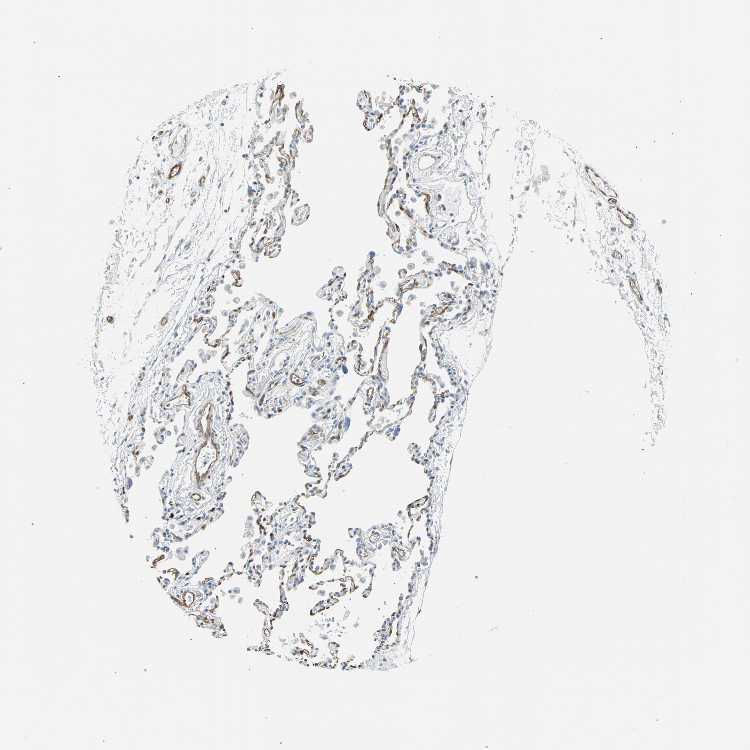

SOFT TISSUE 1 - Antibody stainingi

Antibody staining in the annotated cell types in the current human tissue is reported as not detected, low, medium, or high, based on conventional immunohistochemistry profiling in selected tissues. This score is based on the combination of the staining intensity and fraction of stained cells.

Each image is clickable and will lead to virtual microscopy that enables deeper exploration of all samples and also displays staining intensity scores, fraction scores and subcellular localization as well as patient and tissue information for each sample.

Antibody HPA007007Antibody HPA026111Antibody CAB005889Antibody CAB058692

Chondrocytes ---Not detected

Fibroblasts Not detectedNot detectedMediumNot detected

Peripheral nerve -Low--